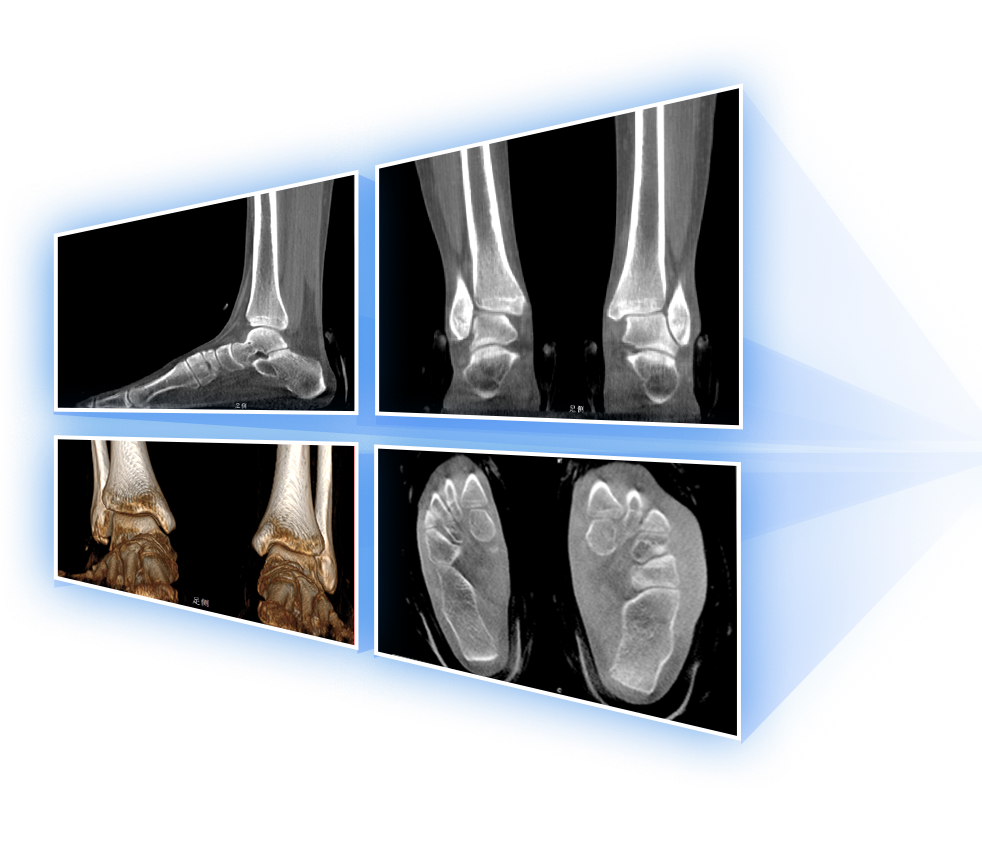

· 补位CT,提供负重位三维影像

· 引领普放走向三维精准诊断时代

独特的负重位三维影像

填补常规CT/MR空白

助力术前规划和术后评估

• 足踝

2D+3D一站式快速检查